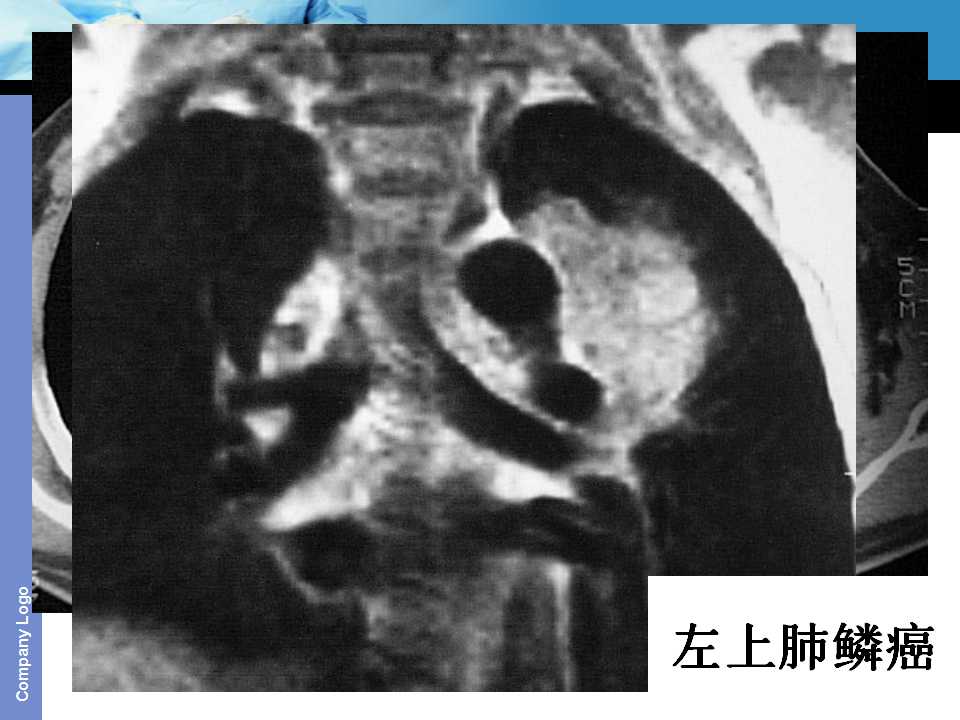

肺癌影像诊断